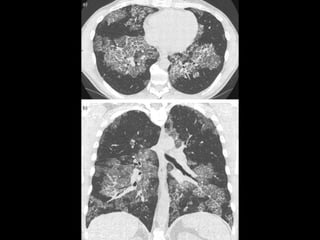

Crazy Paving

Pattern -

Pulmonary

Alveolar

Protienosis